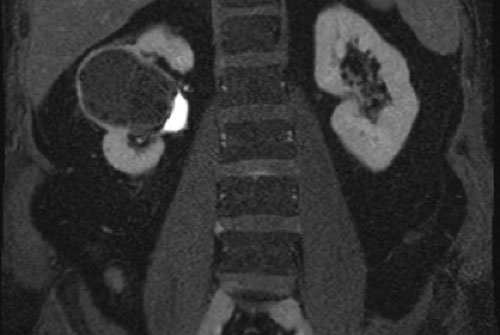

Các ảnh T2W mặt phẳng axial và coronal cho thấy một tổn thương dạng nang ở cực dưới thận trái với thành dày không đều.

Do thành phần mô đặc chiếm dưới 25% tổn thương, tổn thương cần được phân loại là khối dạng nang thay vì u thận đặc dạng nang.

Trên các ảnh T1W coronal có ức chế mỡ trước và sau tiêm thuốc tương phản từ, độ dày thành đo được trên 4 mm (mũi tên).

Tổn thương được phân loại là khối dạng nang Bosniak IV.

Khối đã được phẫu thuật cắt bỏ và được xác nhận là ung thư biểu mô tế bào sáng.